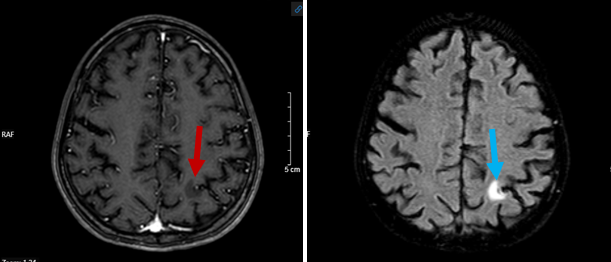

Hình 6: Hình ảnh chụp cộng hưởng từ sọ não: Tổn thương giảm tín hiệu trên xung T1 tiêm thuốc (mũi tên đỏ) và tăng tín hiệu trên xung T2 và Flair (mũi tên xanh) tại vị trí ranh giới chất trắng -  chất xám vị trí thùy đỉnh trái – chưa loại trừ tổn thương thứ phát (bệnh nhân không có tiền sử đột quỵ não ).

Kết luận: Hình ảnh ổ tổn thương ranh giới chất trắng – xám thùy đỉnh trái – chưa loại trừ tổn thương di căn.